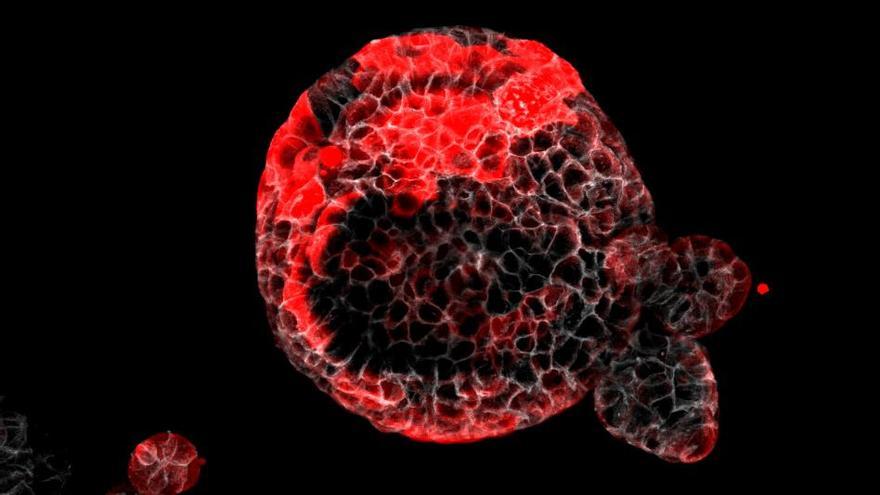

Investigadors de l'Institut de Recerca Biomèdica de Barcelona (IRB) han identificat les cèl·lules que escampen el càncer de còlon en el procés conegut com a metàstasi fins i tot després que s'hagi extirpat el tumor primari a través de cirurgia, en un estudi que publica aquest dimecres la revista 'Nature'. A més han comprovat en experiments amb ratolins que eliminar aquestes cèl·lules mitjançant tècniques genètiques és suficient per prevenir la formació de metàstasi. La situació coneguda com a recaiguda afecta entre el 20 i el 35% dels pacients. El càncer de còlon és el tercer més comú al món, amb prop de dos milions de nous casos cada any.

"El nostre model, molt semblant al progrés de la malaltia en pacients, ens ha permès caracteritzar el tumor primari i la dinàmica de la malaltia residual. Hem estudiat des de micrometàstasis de 3 o 4 cèl·lules, a metàstasis mitjanes, o fins i tot més grans, i hem caracteritzat com evoluciona cadascuna durant la progressió de la malaltia", ha afirmat Adrià Cañellas-Socias, primer autor de l'estudi.

La investigació ha permès determinar que les cèl·lules responsables de la recaiguda són capaces de desprendre's del càncer al còlon, migrar fins al torrent sanguini, arribar al fetge i romandre ocultes durant un temps després de la cirurgia.